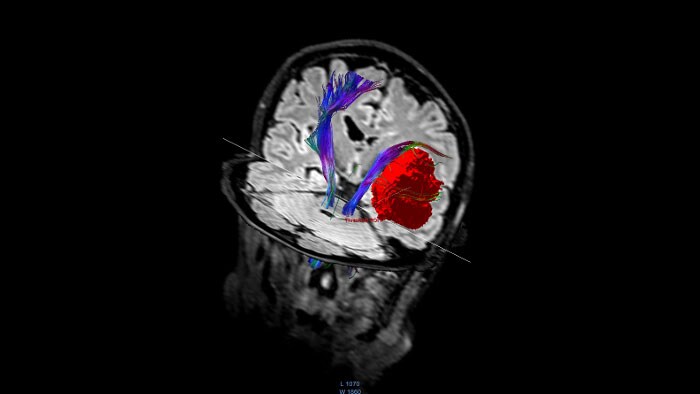

FiberTrak por RM

Permite visualizar os tratos de matéria branca, utilizando as orientações da tarefa para gerar tratos comuns ou definidos pelo utilizador.